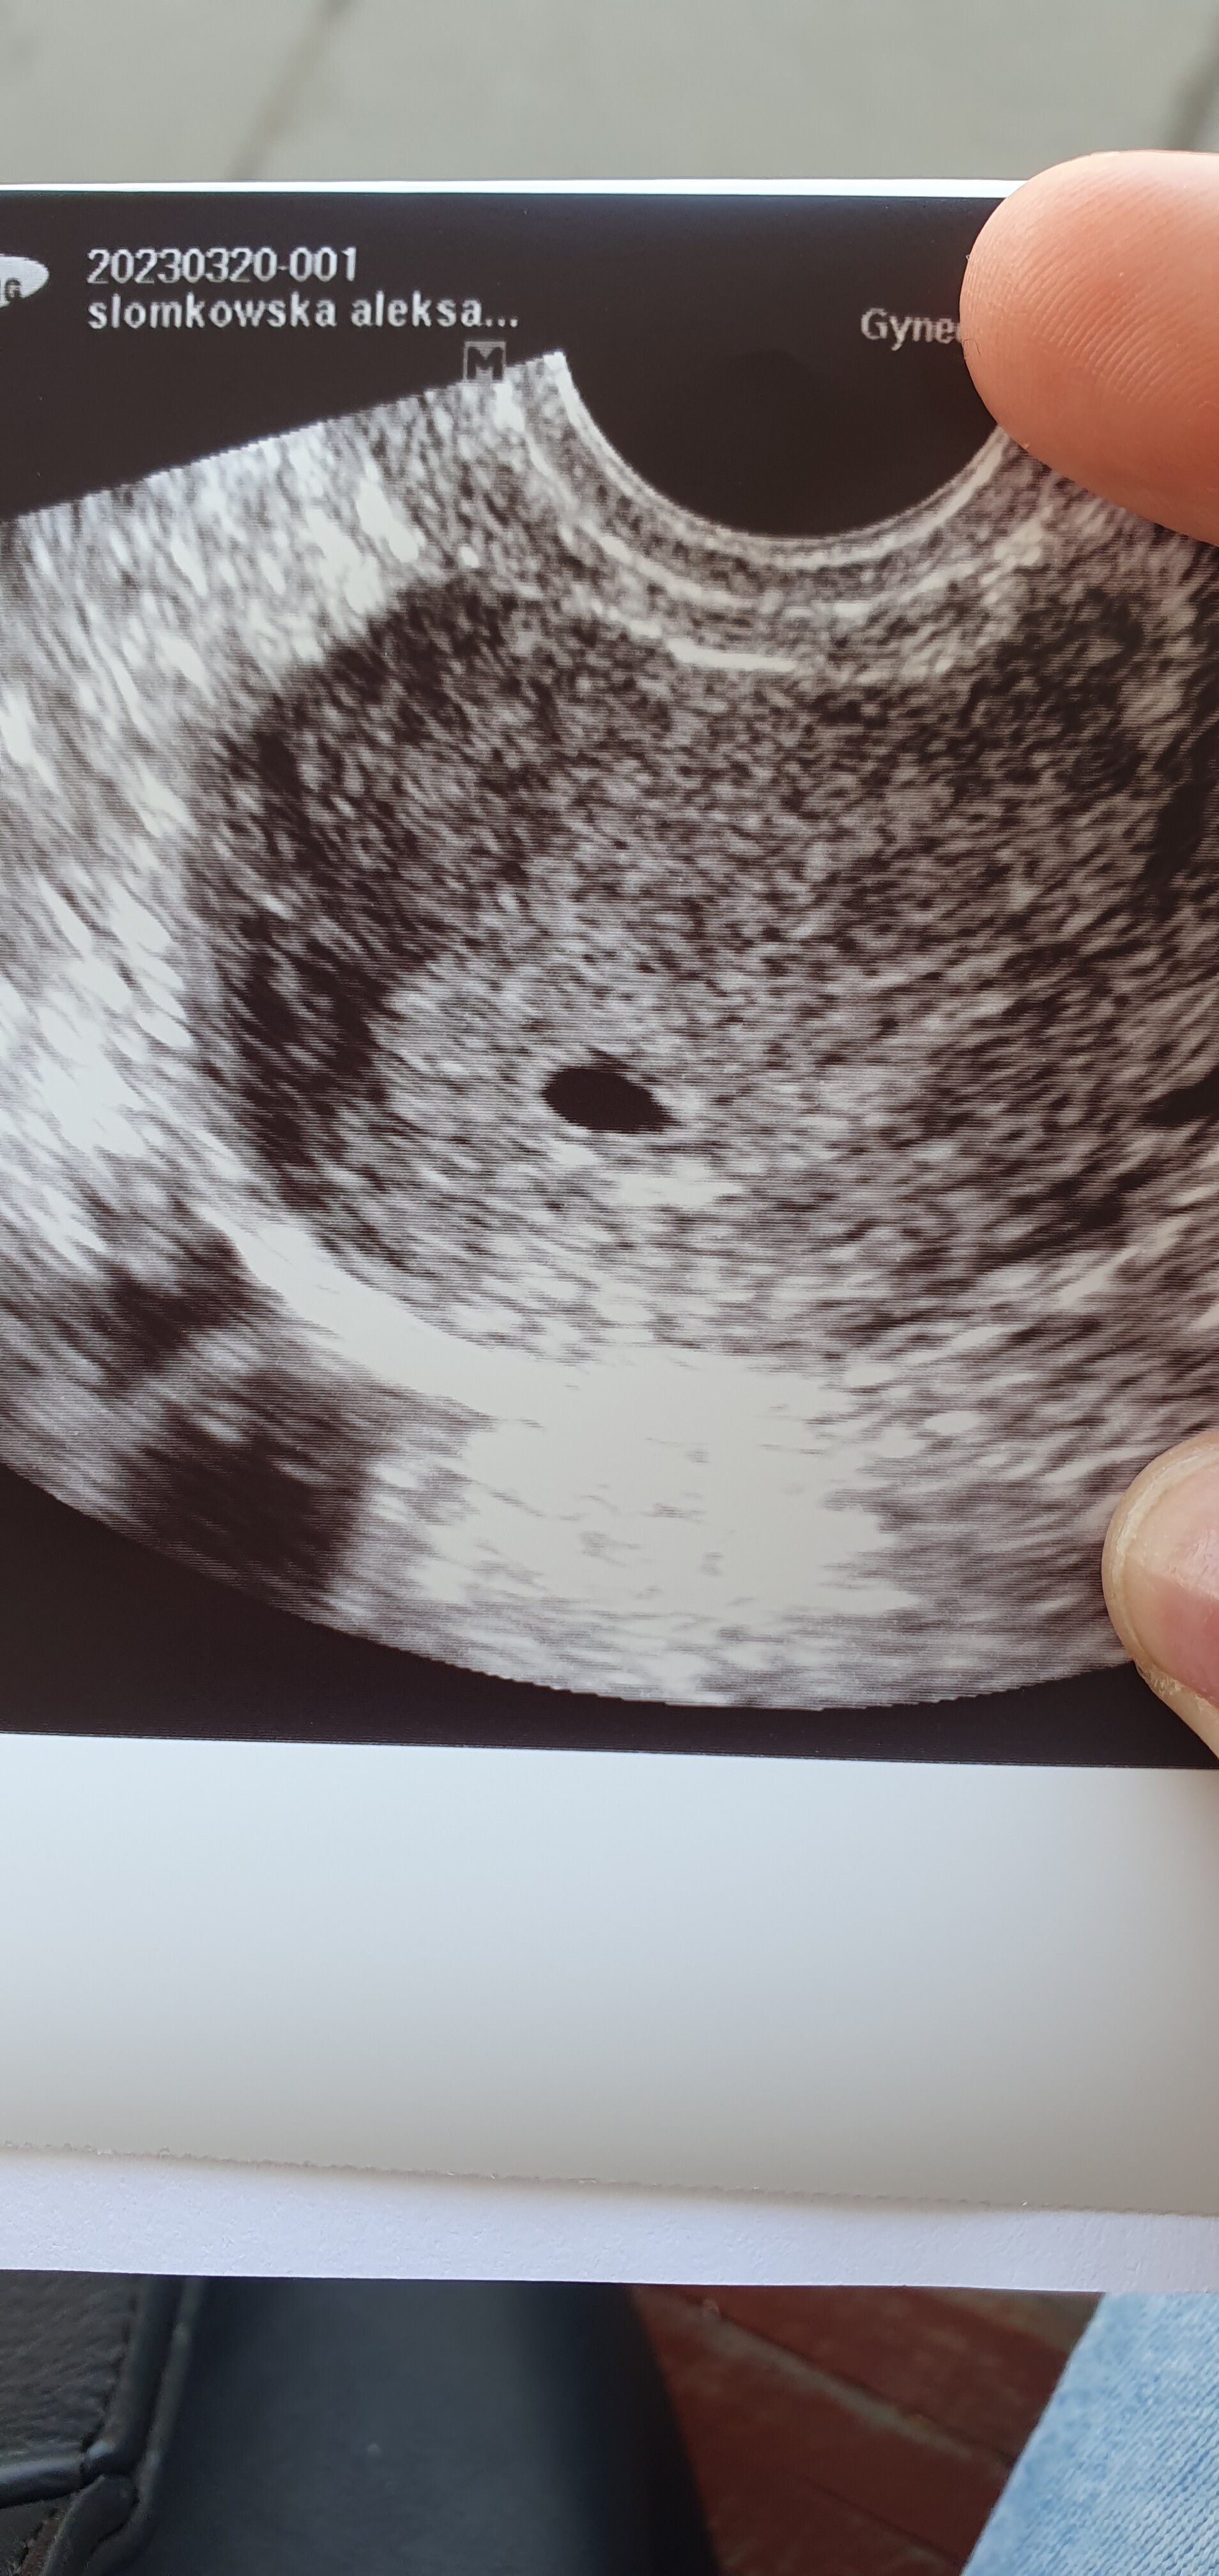

Wróciłam, trochę się przeciągnęło... Na USG jest pęcherzyk z zarodkiem 6,7mm- wymiar odpowiada idealnie terminowi który wyliczyłam- 6t+4.

Ale... żeby nie było tak pięknie... Mam krwiaka co prawda oddalonego od zarodka ale się ciągle opróżnia zamiast wchłaniać i jest sporym zagrożeniem dla ciąży. Kolejną wizytę mam w środę żeby zobaczyć czy zarodek się rozwija bo serce trochę za wolno bije-104/min.